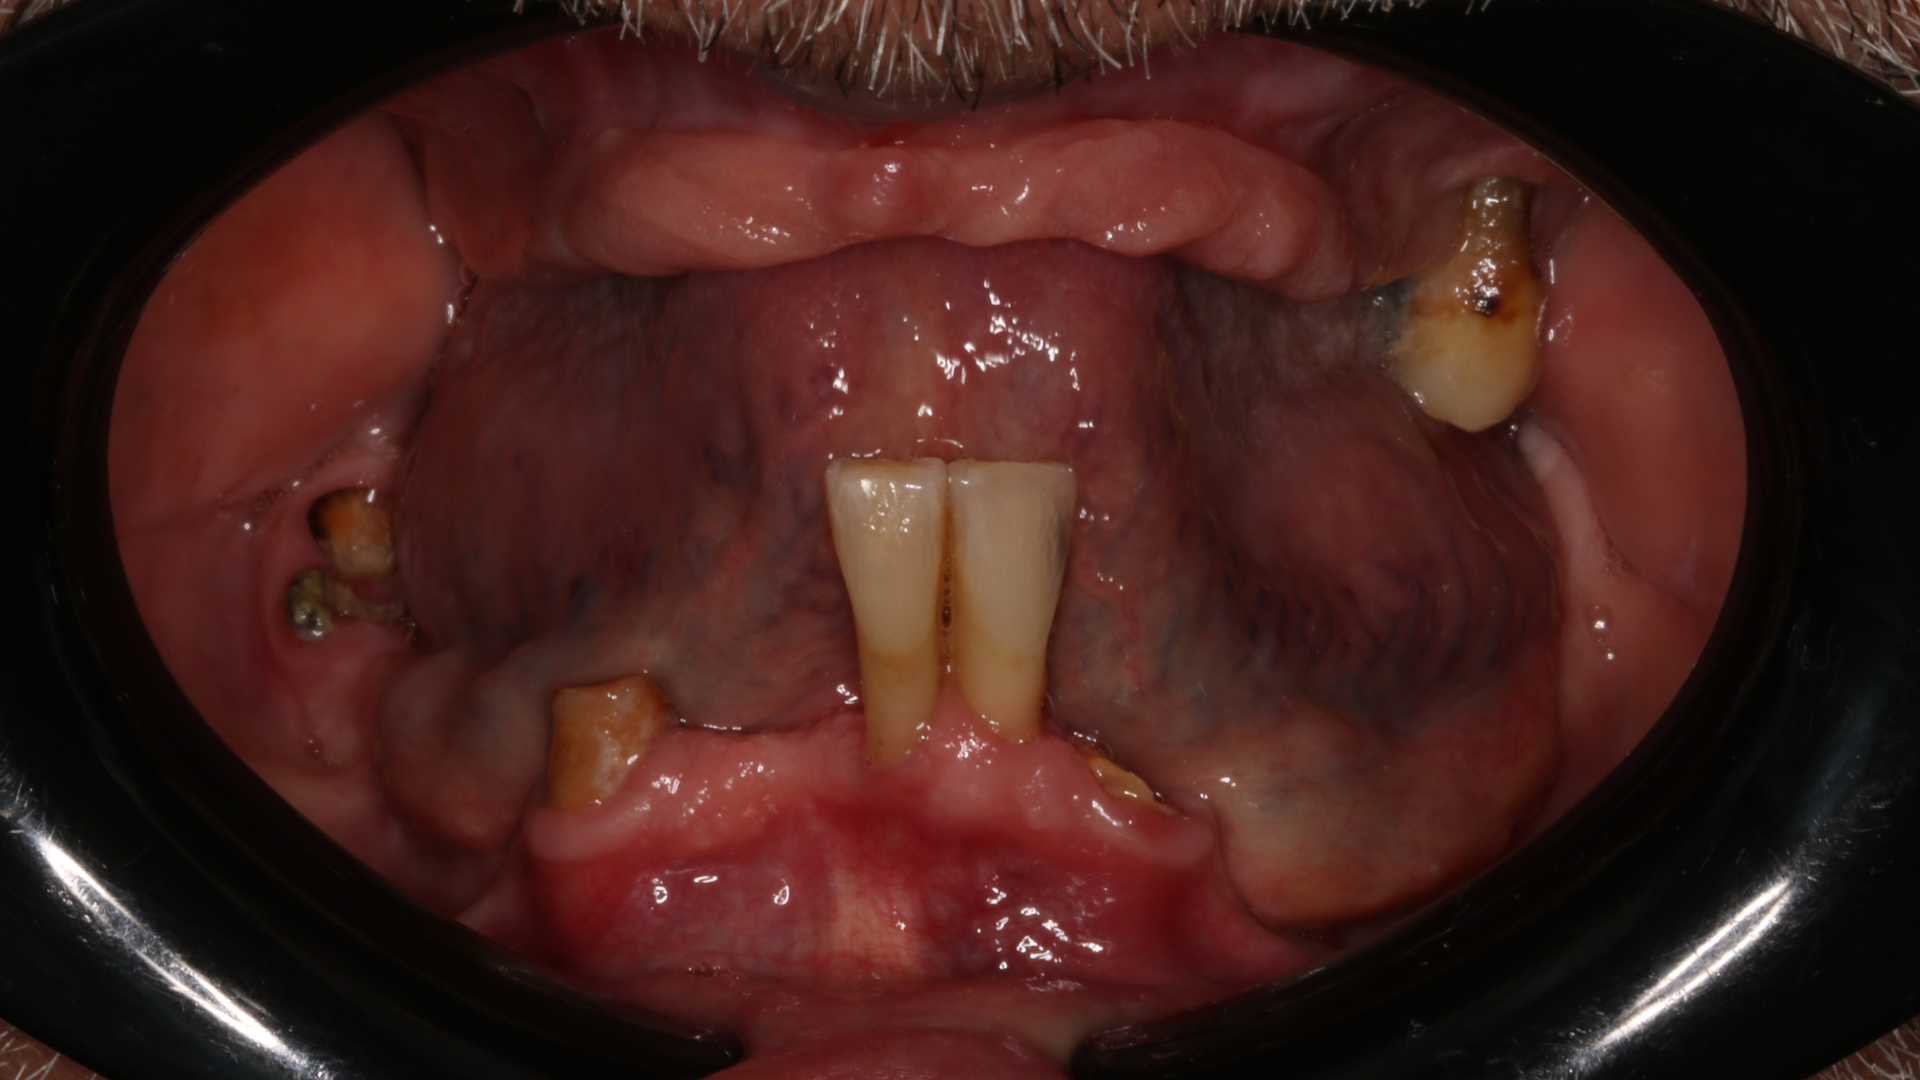

Réhabilitation complète bi maxillaire